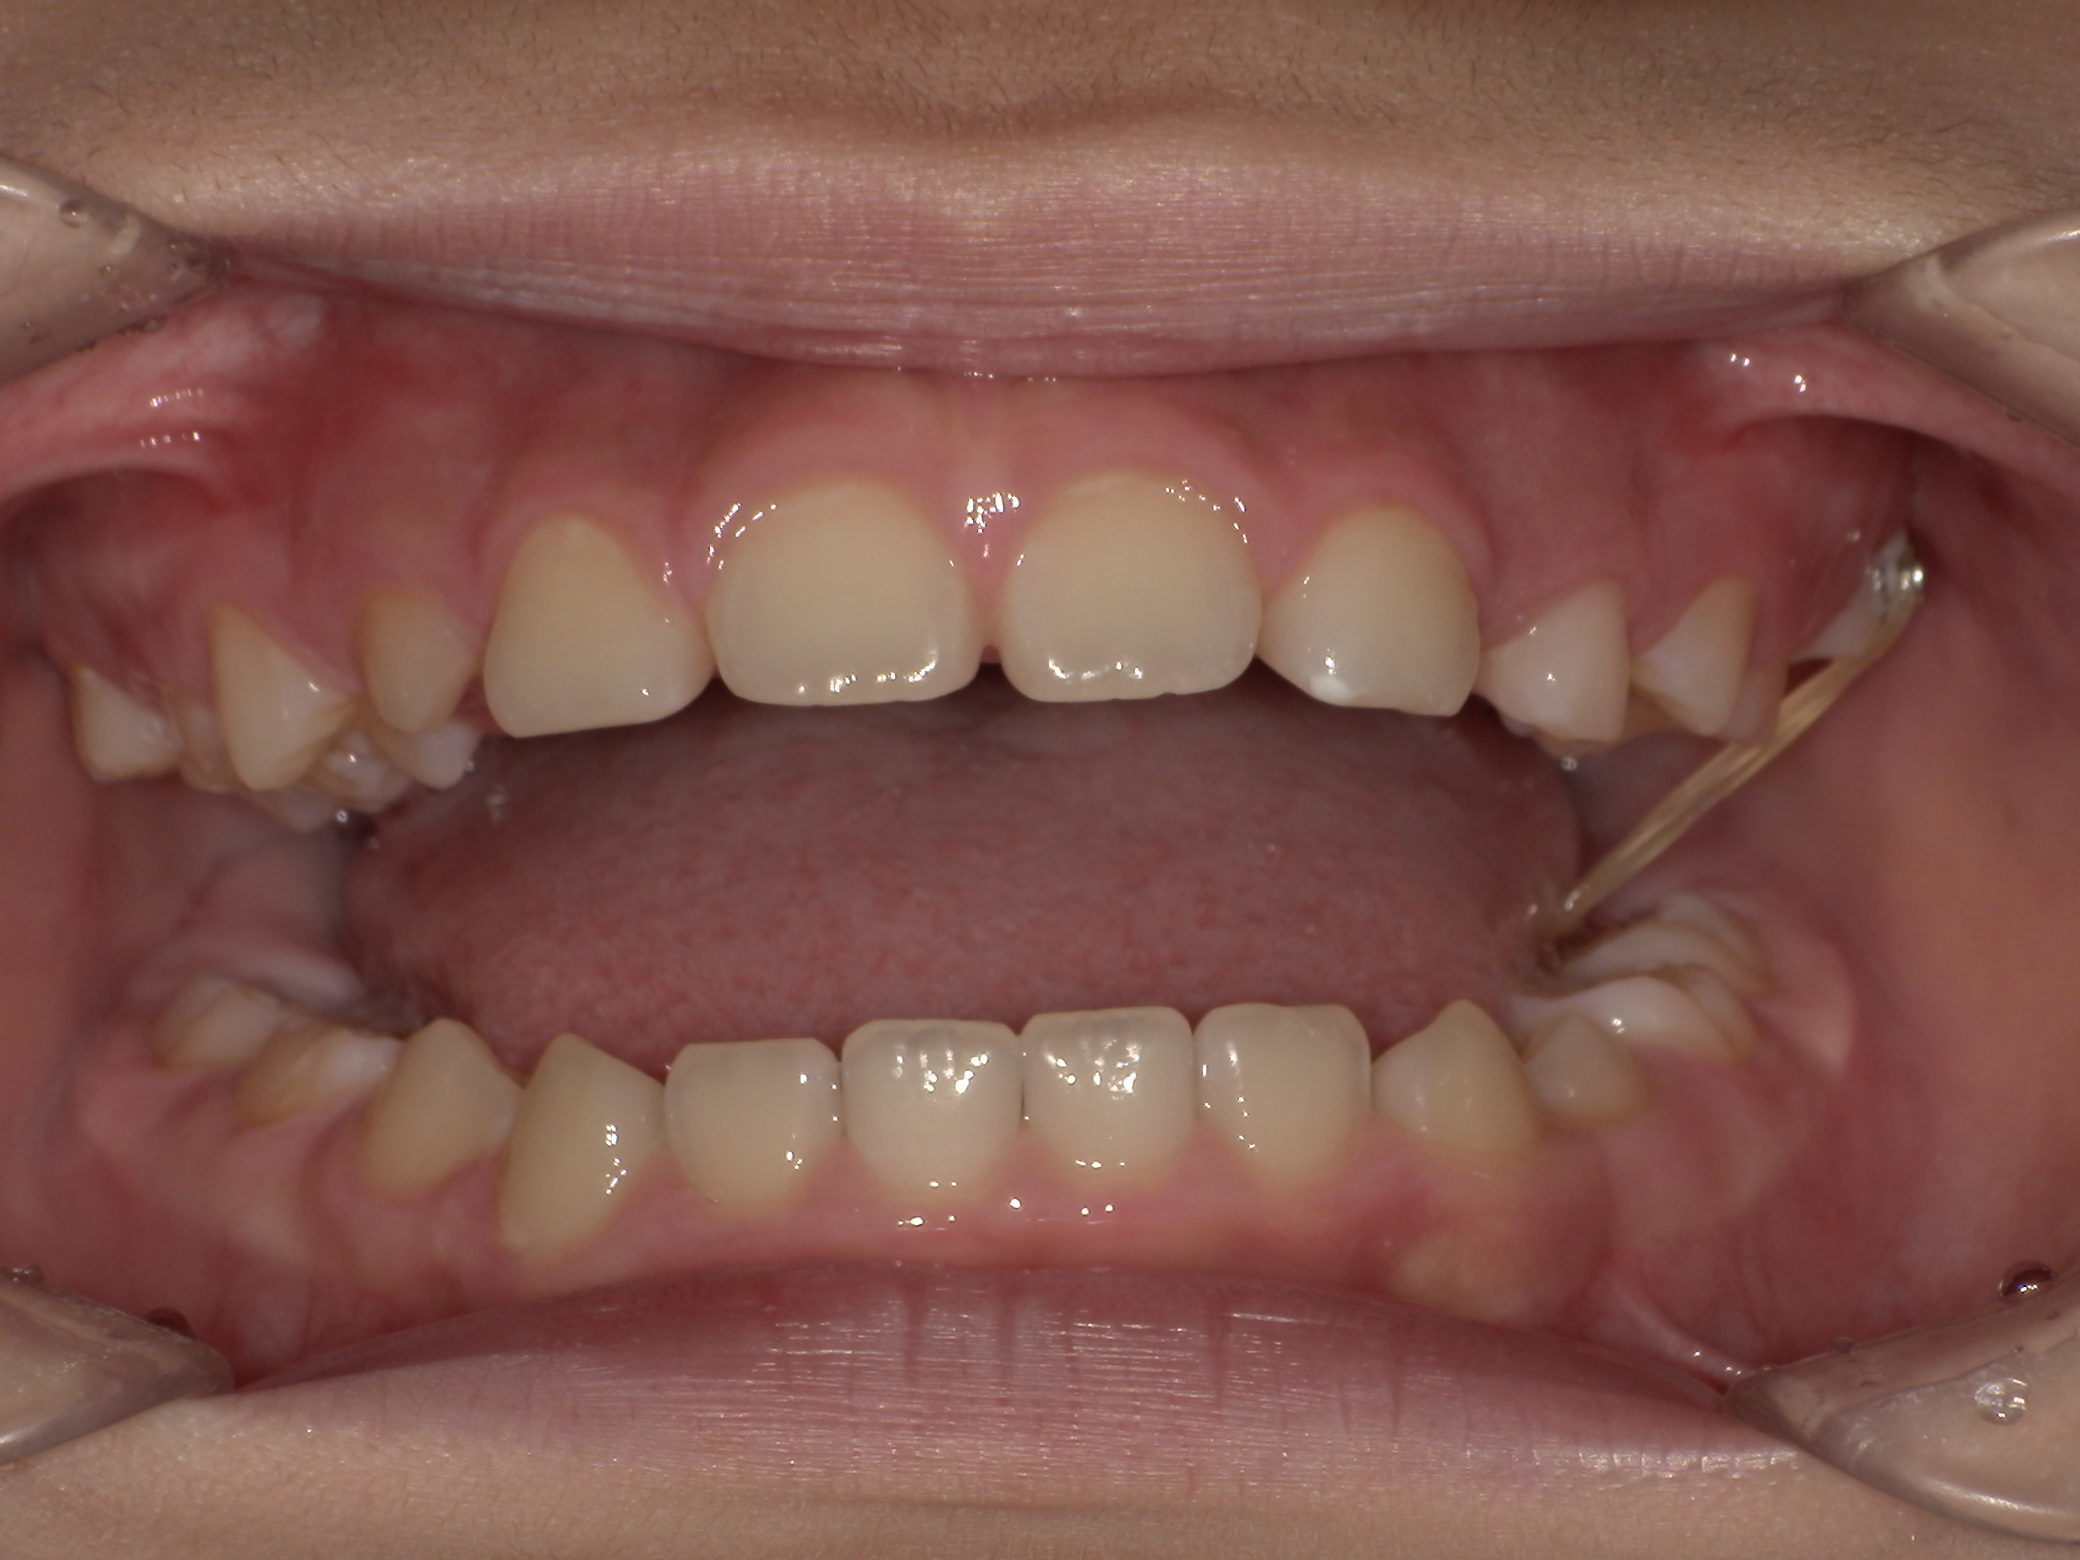

プレオルソ症例|前歯が反対になっている歯並びが気になる

2026/02/06 小児矯正